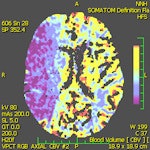

"The introduction of perfusion CT (PCT) of the brain has significantly improved the sensitivity and specificity in detecting fresh ischemia. Perfusion deficit can be detected immediately after stroke, i.e., in the time when a standard CT is still negative," Vymazal stated.

Ultrafast CT scanners together with iterative reconstructions can significantly reduce the radiation dose, but in PCT of the brain the dose still remains relatively high (mean effective dose is approximately 5 mSv). The long reconstruction times of iterative techniques are inconvenient for stroke patient management, but there are techniques that can decrease the radiation dose to values comparable to unenhanced brain CT (approximately 2 mSv), according to Vymazal and colleagues.

"A decrease from 140-120 kV to 100-80 kV not only significantly lowers the radiation dose, but also increases the prominence of the contrast agent because of the greater importance of the photoelectric effect for 80-kV photons," they wrote. "Another method for dose reduction relies on decreasing the image frequency of acquisition from the PCT first-pass data. PCT enjoys a number of advantages as it is fast, widely available, and cost-effective. Furthermore, there are few restrictions in the CT environment."

A number of pitfalls must be considered in performing PCT. The operator-dependent selection for the arterial input function may have a substantial impact on results, especially in patients with chronic vascular conditions such as giant aneurysm or carotid artery occlusion, as well as in those with asymmetric microvascular changes. Postictal changes are another concern; lateralized postictal hyperperfusion may lead to the erroneous diagnosis of contralateral ischemia on visual inspection of color maps, they warned. Additionally, postprocessing and modeling methods may affect the results and complicate comparison across studies.